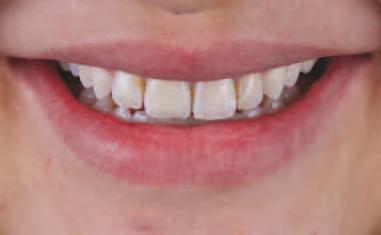

Un ob ect v pr nc pal al restaurăr lor dentare este să m te d nț natural în armon e cu fața nd v dulu . S-a demonstrat de mult t mp că un zâmbet atrăgător are un mpact semn f cat v asupra percepț e ș a d scernământulu celorlalț . De-a lungul an lor, în stomatolog a estet că s-au făcut progrese substanț ale, în spec al în ceea ce pr vește avansarea tehnolog lor d g tale care fac l tează pro ectarea

tr d mens onală (3D) a zâmbetulu , personal zată, în armon e cu fața pac entulu . Deoarece percepț a estet c dentofac ale este determnată ș de prefer nțele personale ș de factor cultural , este esenț ală ntegrarea pac entulu în procesul dec z onal pentru a at nge ob ectvele opt me de tratament estet c. În ult mele decen , pro ectarea zâmbetulu s-a mutat progres v de la fluxur de lucru analog ce la d g ta-

le, care s-au dezvoltat ulter or de la nstrumentele b d mens onale (2D) la cele tr d mens onale (3D). Implementarea nstrumentelor d g tale ș a nteracț un onl ne a îmbunătăț t comun carea între cl n c en , tehnc en dentar ș pac enț . Îmb narea fotograf lor 2D cu f ș erele d g tale 3D perm te tranz ț a către un flux de lucru complet d g tal ș fac l tează pro ectarea d g tală a zâmbetulu gh dată fac al. Instrumentele no de

pro ectare d g tală a zâmbetulu pot f folos te pentru a contura ș mod f ca d g tal zâmbetele pac enț lor dar ș pentru a v zual za rezultatul îna nte de pract carea unor procedur revers b le. De asemenea, astfel de nstrumente perm t anal za met culoasă a caracter st c lor fac ale ș dentare ale pac entulu pentru a fac l ta pro ectarea d g tală. În mod ob șnu t, un f ș er STL al pro ectăr d g tale a zâmbetulu este mpr mat în 3D, ar acest model este folos t pentru producerea une s mulăr în scaunul stomatolog c. Ver f carea tuturor parametr lor estet c este esenț ală, deoarece aceeaș pro ectare 3D a zâmbetulu sau o mod f care corespunzătoare a aceste a este ut l zată pentru fabr carea restaurăr lor def n t ve. De fapt, toț paș ulter or , nclus v t pul de tratament restaurator, mater alul ș pro ectarea preparaț e dep nd d rect de prec z a aceste pro ectăr n ț ale.